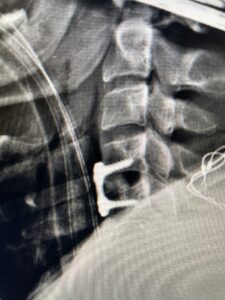

This 47-year-old male who four months prior was lifting weights developed sharp pain in his neck. After that he developed progressive numbness in his arms, neck pain and headache. He said that the right arm was worse than the left. On examination the patient had long tract weakness on the right side which included his triceps, finger extensors, hip flexors, and dorsiflexors. The patient did not have hyperreflexia. MRI (Fig. 2) demonstrated a massive, extruded disc herniation with severe cord compression. The patient because of progressive myelopathy and spinal cord compression was indicated for anterior cervical discectomy and fusion at C4-5 (Fig. 3). Patient had significant improvement of weakness and numbness post operatively.

Fig. 2a Sagittal T2-weighted cervical MRI demonstrating large C4-5 herniated disc with spinal cord compression (red arrow)

Fig. 3 Intraoperative lateral cervical X-Ray demonstrating C4-5 ACDF